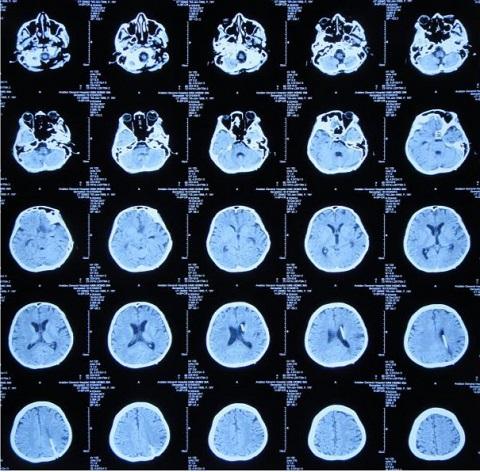

据患者家属介绍,患者入院2月前出现头痛、呕吐、发热症状,最高体温38.4度,至神木县医院急诊外科,检查途中突然出现四肢软瘫、呼喊不止,随即意识丧失、大小便失禁,紧急收入ICU,新腰椎穿刺检查:CSF常规:细胞总数1548×106/L,淋巴细胞百分比56.8%,蛋白2266mg/l,糖1.15mmol/l,考虑结核性脑膜炎,收入ICU。

4月25日转至北京,腰椎穿刺测压>330mmHg,5月15日颅压185mmH2O,体温正常,但左眼睑下垂无改善。

5月18日转入航空总医院神经外七科,患者神清,精神差,对答可,双瞳孔L:R=4:3,左侧对光反射消失,右侧可,视物重影。左眼睑、鼻部、下颌及左侧肢体感觉减退。右侧肢体肌力4级,左侧肢体肌力3级+。双侧病理征阴性。

5月22日给予患者行侧脑室外引流术,术后脑脊液色黄微浊。

6月20日,引流脑脊液仍然色黄浑浊,复查头CT环池、鞍区仍然密度升高、间隙消失。

8月16日,患者脑脊液仍然色黄浑浊,复查增强MRI现实四叠体池区、鞍区、环池内多发结核脓肿。

10月18日,患者脑脊液外观基本清亮,增强头MRI现实仍然课件鞍区多发结核脓肿、四叠体池、环池内病变明显改善。

10月20日,行分流手术,术后复查增强头MRI见图。